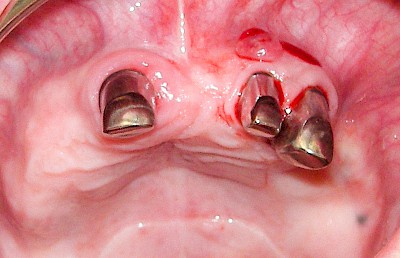

Schwellung mit Eiter: Abszess

Schwellungen im Zusammenhang mit akuten Entzündungen im Bereich der Zähne oder dem Zahnhalteapparat entstehen meist aufgrund schneller und starker Vermehrung von Bakterien sowie einer starken Abwehrreaktion des Körpers (Abszess). Diese Schwellungen entstehen meist in sehr kurzer Zeit – innerhalb von Stunden oder wenigen Tagen. Die Schwellungen sind sehr schmerzhaft. Nah am Zahnfleisch kann sich bei leichtem Druck auf die Schwellung Eiter entleeren. Mitunter fühlen sich die Menschen krank. In fortgeschrittenem Stadium kann auch Fieber auftreten. Hier ist sofort der Zahnarzt zu kontaktieren, um eine weitere Ausbreitung der Entzündung zu verhindern.